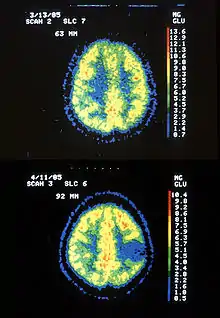

Two PET images—the upper of which shows a normal brain and the lower shows astrocytoma.